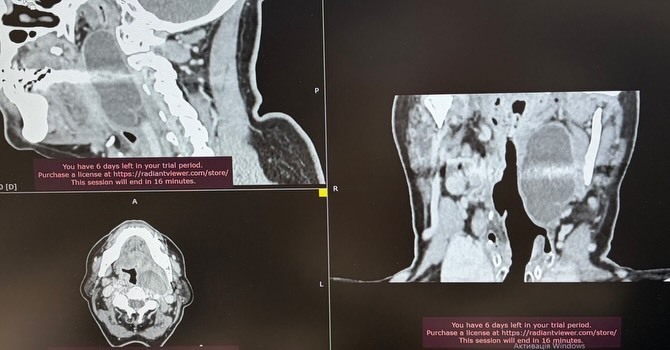

Фахівці Подільського регіонального центру онкології успішно провели складне хірургічне втручання, видаливши рідкісну пухлину парафарингеального (позаглоткового) простору. Такі новоутворення зустрічаються досить рідко і вважаються одними з найскладніших для оперування через їхнє розташування.

Особливість подібних пухлин полягає в тому, що вони тривалий час можуть не проявляти себе жодними симптомами. Однак у міру росту новоутворення починає тиснути на сусідні органи та тканини. У випадку вінницької пацієнтки пухлина досягла значних розмірів, через що жінці стало важко дихати та ковтати їжу.

Складність операції була зумовлена специфікою анатомічної зони. Позаглотковий простір межує з магістральними судинами та важливими нервовими вузлами. Будь-яка помилка під час маніпуляцій могла призвести до серйозних наслідків. Саме тому лікарі приділили особливу увагу передопераційному плануванню.